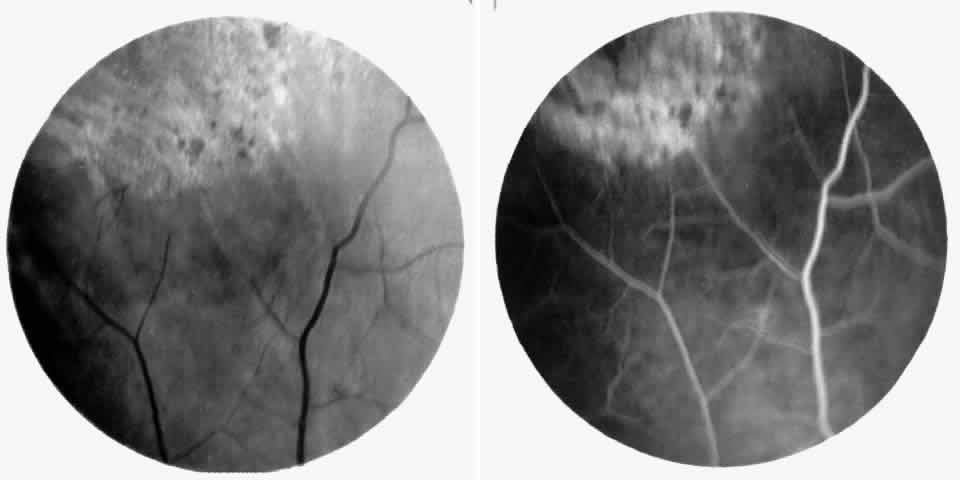

STAGE III: PRERETINAL NEOVASCULARIZATION (PROLIFERATIVE SICKLE RETINOPATHY). “Sea fan”-shaped neovascularization typically develops on the venular side of an arteriolar-venular anastomosis, mimicking the normal development of retinal capillaries (Fig. 24).125 A lowered oxygen tension and angiogenic factors released on the venular side may be the stimulus for neovascular growth.125,126 In most instances, the direction of growth is toward the ora serrata, from the perfused retina toward the nonperfused retina. Presumably, this represents an abortive attempt to revascularize the nonperfused retina, initiated by vasoproliferative factors.

The characteristic neovascular lesions of PSR are called sea fans because they resemble the marine invertebrate Gorgonia flabellum.70 They tend to occur more commonly in the temporal periphery, but they have been reported to occur in the temporal macula in the presence of extensive nonperfusion.130,133 Initially they grow on the surface of the retina, but they often become elevated into the vitreous and adhere to a partially detached posterior hyaloid.114 It may be difficult to visualize small sea fans ophthalmoscopically; however, fluorescein angiography clearly demonstrates leakage of dye into the vitreous (Fig. 25). The feeding arteriole is usually more tortuous than the draining venule (Fig. 26). Early on, the neovascular lesion is fed by a single arteriole and drained by a single venule, but with time, additional arterioles and venules become arborized within the lesion (Fig. 27).129 Growth of the sea fan often occurs circumferentially, rather than radiallyÜmh- 1Ý, toward the ora serrata. Progressive circumferential growth may lead to neovascular lesions extending around the entire periphery. As it matures, a white fibroglial mantle often covers the neovascular tissue (Color Plate 2B).

|

|

PSR is associated with the severe vision-threatening sequelae of sickle cell disease: vitreous hemorrhage (stage IV) and retinal detachment (stage V). These stages are believed to result from transudation of blood components into the vitreous through the incompetent neovascular tissue (Fig. 28). Vitreous fluorophotometry has quantified the leakage from the peripheral neovascularization.134 This leads to premature syneresis and collapse of the vitreous, inducing tractional forces on the retina that lead to vitreous hemorrhage, retinal tears, and tractional and rhegmatogenous retinal detachment. In rare cases, an exudative detachment may occur.

|

Spontaneous nonperfusion or autoinfarction, accompanied by regression of the neovascular lesion, occurs in 20% to 60% of eyes with PSR.135,136 The peak incidence of autoinfarction is 2 years after the development of PSR. It appears that autoinfarction occurs primarily as a result of (1) occlusion of the feeding arteriole due to traction on the neovascular lesion by contracting vitreous, or (2) occlusion by sickled RBCs. The latter probably is more common in homozygous sickle cell anemia, which is more commonly associated with autoinfarction and complete vascular occlusion.

Sea fans develop an average of 14 months after diagnosis of stage II, with an approximate incidence of 14% per year in patients with SC disease.129 In a series of selected patients with different hemoglobinopathies in Jamaica, the incidence of PSR was reported as follows: 2.6% with sickle cell anemia83; 14.0% with Hb S-β-thalassemia91; and 32.8% with SC disease (see Table 1).92 It is a common misconception that patients with homozygous sickle cell anemia have a very low risk of developing retinal neovascularization. Although the risk is recognizably lower, it must be remembered that the development of neovascularization is not only genotype-dependent but also age-dependent, increasing with age in both genotypes with the highest risk period of 20 to 34 years of age in SC disease and 40 to 50 years of age in homozygous sickle cell anemia.26,137 The incidence of PSR in patients with homozygous sickle cell anemia is 14% for patients older than 40 years and up to 29% in patients older than 50 years.25,76 In a series of 786 patients with homozygous sickle cell anemia, the prevalence of PSR was demonstrated to increase gradually, peaking in patients aged 30 years and older. The first cases were observed in patients in their late teens, the incidence rate increasing in patients who were 25 years and older.29 In the same study, a series of 533 patients with SC disease demonstrated that the prevalence of PSR reached a maximum in men in their late 20s and in women older than 40 years, whereas the incidence rates of PSR peaked in men in their early 20s and in women in their late 20s. The prevalence of PSR has been reported to be as high as 68% in SC disease patients 45 years of age and older.26 An ongoing cohort study in Jamaica will undoubtedly provide information on the evolution of PSR in patients with the various genotypes.